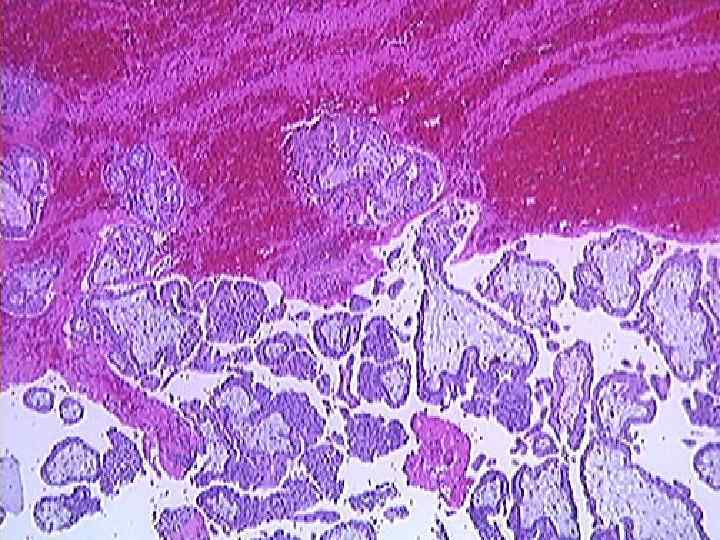

Семинома

Хорионкарцинома 1886 год – М. Н. Никифоров Микроскопически: n клетки цитотрофобласта n гигантские клетки синцитиотрофобласта